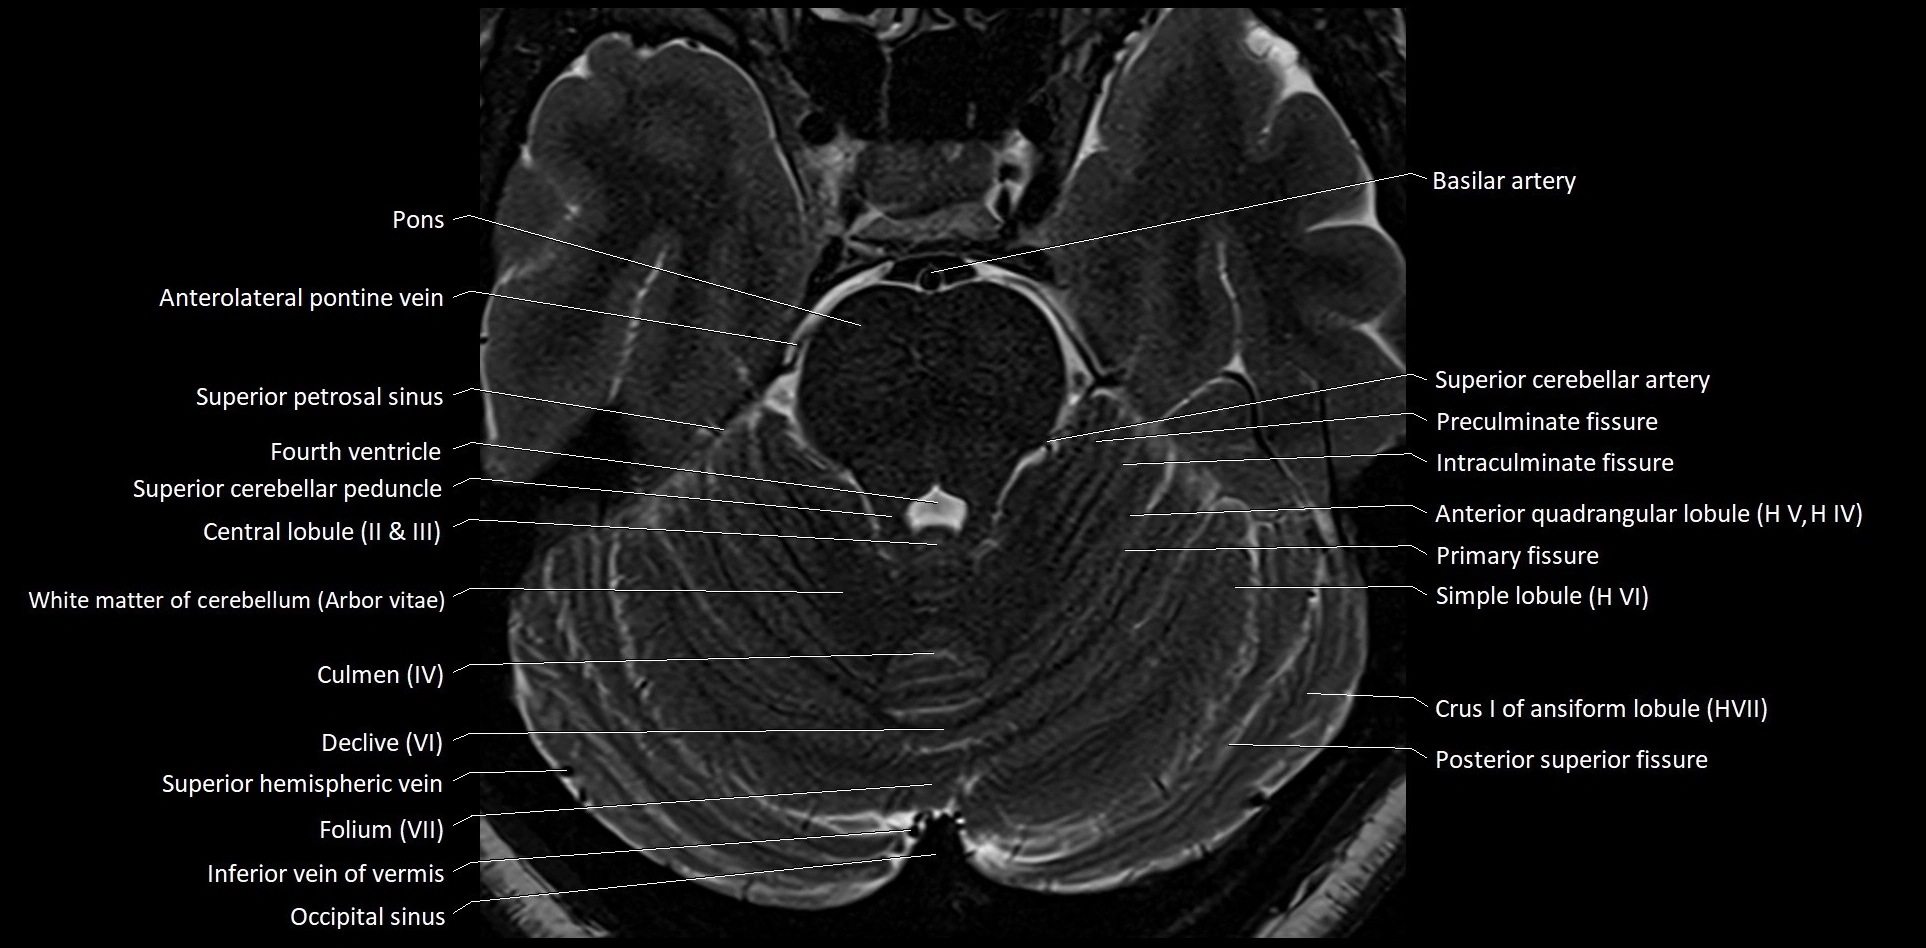

MRI images